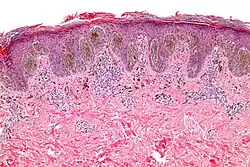

Melanocytic nevi can mainly be classified by depth, being congenital versus acquired, and/or specific dermatoscopic or histopathologic patterns:

- Depth

| Depth class | Location of nevus cells | Other characteristics | Image | ICD code |

|---|---|---|---|---|

| Junctional nevus | Along the junction of the epidermis and the underlying dermis.[15] | May be colored and slightly raised.[16] |

|

ICD10: D22 ICDO: M8740/0 |

| Compound nevus | Both the epidermis and dermis.[17] |

|

ICD10: D22 (ILDS D22.L14) ICDO: 8760/0 | |

| Intradermal nevus | Within the dermis. | A classic mole or birthmark. It typically appears as an elevated, dome-shaped bump on the surface of the skin.[3][4] |

|

-

Small dermal nevus, with nests of nevus cells (arrows)

Small dermal nevus, with nests of nevus cells (arrows)